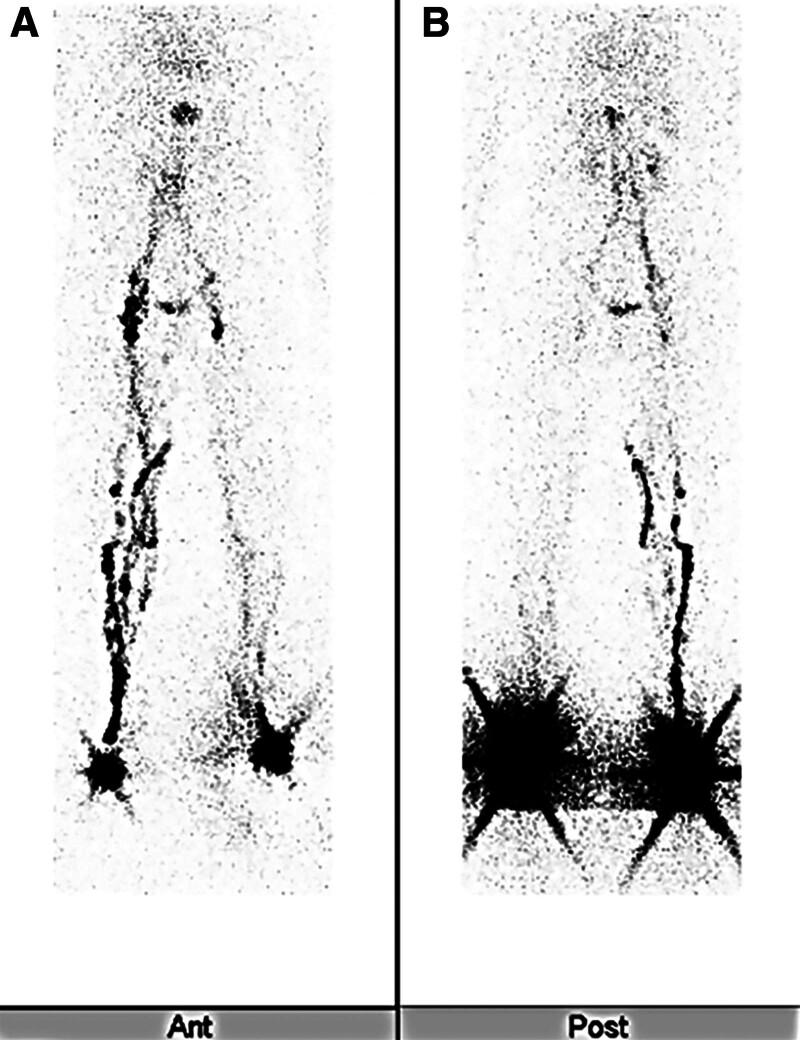

In the present study, we encountered a patient who developed intraabdominal lymphatic leakage after surgery for gastric cancer, underwent lymphangiography and lymphatic mass embolization, and developed severe lymphedema. The patient was a 55-year-old woman with gastric cancer with pancreatic invasion. Total gastrectomy and lymph node dissection were performed as conversion procedures. Six liters of ascites was detected postoperatively. Lymphangiography with Lipiodol injections into the bilateral inguinal lymph nodes was done three times, and Histoacryl embolization of the lymphatic leak was performed. However, edema of the lower extremities rapidly worsened. Lymphatic venous anastomosis was performed under general anesthesia. Anastomosis was performed at seven sites on the right and eight sites on the left. Postoperatively, the patient underwent compression therapy using the multilayer bandage method. The edema continued to improve further, and at 2 weeks postoperatively, the patient's weight had decreased by 21.4 kg from the preoperative weight, which was the same as that before the onset of edema. In this case, the patient's general condition was unstable due to cardiac insufficiency and other factors. Therefore, we aimed for an operation time of less than 3 hours. In addition, two surgeons performed the surgery to ensure an immediate therapeutic effect, and more anastomoses were performed than usual. After lymphatic venous anastomosis, not only the edema of both lower extremities but also the edema of the entire body improved promptly. One of the reasons for the improvement in general edema was thought to be due to increased intravascular protein and enhanced intravascular return of interstitial fluid.

在本研究中,我们遇到一名胃癌手术后发生腹腔内淋巴漏的患者,该患者接受了淋巴管造影和淋巴肿块栓塞治疗,并出现了严重的淋巴水肿。患者为一名55岁的女性,患有侵犯胰腺的胃癌。作为改良性手术进行了全胃切除术和淋巴结清扫术。术后检测到6升腹水。向双侧腹股沟淋巴结注射碘油进行了3次淋巴管造影,并对淋巴漏进行了组织黏合剂栓塞治疗。然而,下肢水肿迅速加重。在全身麻醉下进行了淋巴管静脉吻合术。在右侧7个部位和左侧8个部位进行了吻合。术后,患者采用多层绷带法进行压迫治疗。水肿持续进一步改善,术后2周时,患者体重较术前下降了21.4kg,与水肿发生前相同。在这种情况下,患者由于心脏功能不全等因素,全身状况不稳定。因此,我们将手术时间目标设定为少于3小时。此外,由两名外科医生进行手术以确保立即产生治疗效果,并且进行了比通常更多的吻合。淋巴管静脉吻合术后,不仅双下肢水肿,而且全身水肿均迅速改善。全身水肿改善的原因之一被认为是由于血管内蛋白质增加和间质液血管内回流增强。